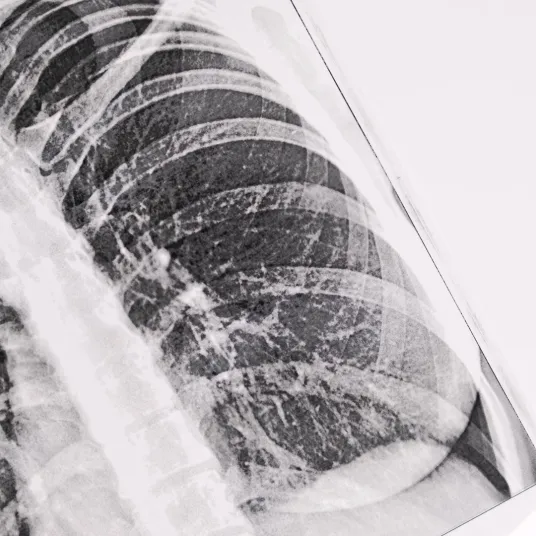

La Pneumologie est la spécialité qui s’occupe des maladies des poumons et de l’appareil respiratoire.

Elle concerne la Trachée, les Bronches, les Poumons, le Diaphragme (muscle inspiratoire principal).

• Radiographie de thorax,